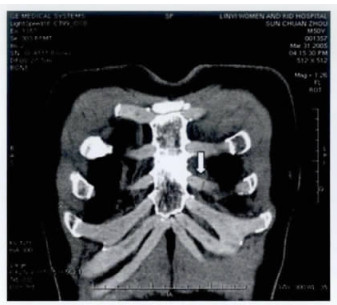

128层螺旋ct三维重建在胸部外伤肋骨及肋软骨骨折诊断中的应用 中国期刊网

多层螺旋ct后处理重建在肋骨和肋软骨骨折诊断中的临床应用 中国期刊网

128层螺旋ct三维重建在胸部外伤肋骨及肋软骨骨折诊断中的应用 中国期刊网